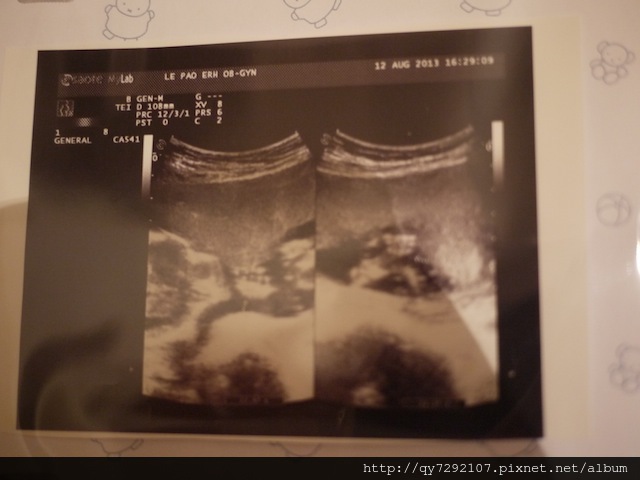

2013/08/12~就是新莊樂寶兒了!

自從決定在台灣生產之後,身體狀況越來越好,也開始吃比較多,身心狀況似乎越來越順利,難道真的是像人家說的,孩子會自己決定出生的時間與地點?!在台灣我依然嚮往“溫柔生產”,今天跟姐姐拜訪了主張溫柔生產的樂寶兒,也參觀了水中生產的房間,如果我身體狀況允許,Pony也配合,還是希望以水中生產的方式迎接Pony的到來,會診了許逸欣醫師,我跟姐姐都非常喜歡她,這就是所謂的醫生緣吧?!今天謝謝許醫師的耐心看診,她幫我看超音波看得非常仔細,Pony的10根手指和腳趾都算的清清楚楚,頭部,心臟和內臟也一併看了,Pony非常健康活潑,我憂心羊膜瓣的問題,也終於放下了!許醫師也說:不用花錢做高層次超音波了。關於Pony的性別,Pony有一瞬間打開腳給我們看一下,之後就害羞的合起來了,許醫師說:看起來比較偏向女生,沒有看到小雞雞喔!不管是男孩女孩,今天我最開心的就是Pony四肢健全,身體健康。Dear Pony:要跟媽媽一起繼續加油喔!